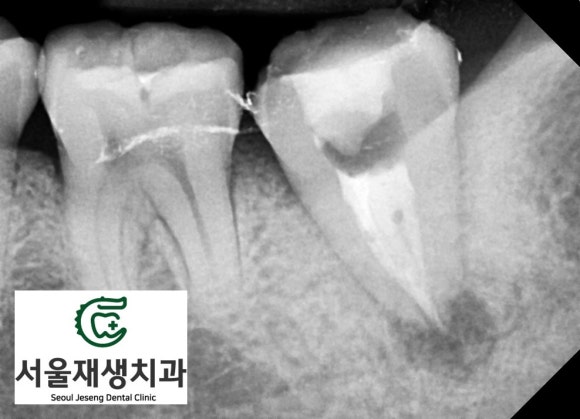

추가 촬영을 통해

해당 치아의 상태를

보다 면밀히 파악할 수 있습니다.

치아 내부의 잔존 조직들이

시간이 지남에 따라 부패하여

뿌리 끝에 나있는 작은 구멍

(=치근단공)을 향해

염증 물질을 내뿜습니다.

그 결과,

뿌리 끝을 중심으로 하는

동그란 염증주머니가

생기는 것이죠.